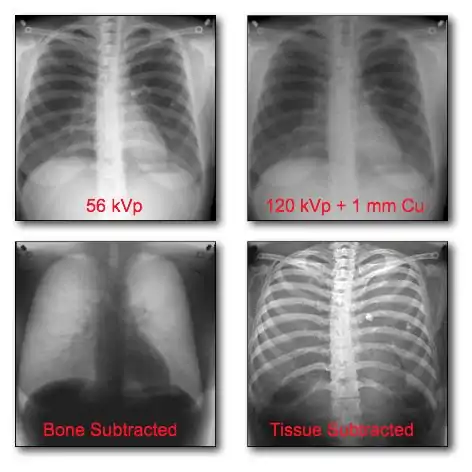

Dual-Energy Radiography

Dual-energy imaging can be used to eliminate bone information in an image, so that an image displaying tissues only is obtained. Alternatively, the technique can be used to generate the reverse effect where tissue information is eliminated and an image displaying bone only is generated. This latter option ideally allows the density of bones to be analysed. A theoretical background to this imaging technique will first be developed below with the discussion leading towards Dual-Energy X-Ray Absorptiometry (DEXA).

Basic Dual-Energy Physics

- Dual-energy imaging is based on exploiting the difference in the attenuation of tissue and bone - see Figure 7.16 - at different X- ray energies. It generally involves acquiring images at two X-ray energies and processing them to suppress either the bone or the tissue information. A simplified mathematical model, similar to that developed earlier earlier for DSA, assumes that monoenergetic radiation is used and no scattered radiation, once again, is detected, so that the transmitted radiation intensity through a region of bone and tissue, acquired at a low X-ray energy and following logarithmic transformation, can be given by: